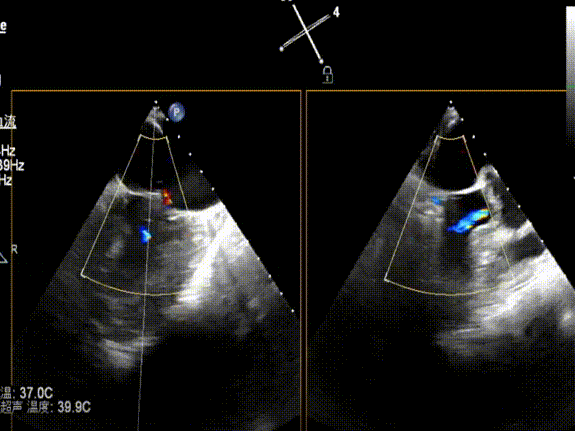

手术经股静脉-房间隔入路,采用全身麻醉插管,在TEE和DSA引导下完成房间隔穿刺。置入JensClip瓣膜夹系统后,在左房调整瓣膜夹的位置和轴向,后进入左室,在TEE引导下捕捉二尖瓣前后瓣叶,并关闭瓣膜夹。经TEE反复确认手术效果后最终锁定并释放瓣膜夹。由于该病例二尖瓣后叶P2区及部分P3区脱垂,脱垂范围宽度达20mm,术中植入了两枚长宽(LW)的瓣膜夹。术后即刻超声显示瓣膜夹位置稳定,功能良好,二尖瓣反流由术前4+减少至微量,肺静脉逆流和左房压都显著好转,手术圆满成功。术后患者状态良好,目前已安排出院。

术后二尖瓣反流降至微量,瓣膜夹稳定,功能良好